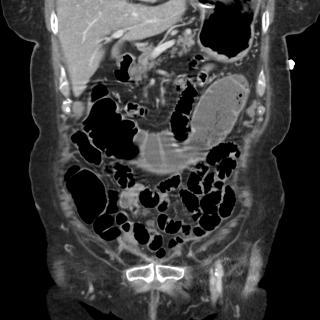

Aspect de occlusion du

de dilatation du grele Image TDM en coupe

Image TDM en coupe coronale

dilate mais l'intestin grele est normale . |